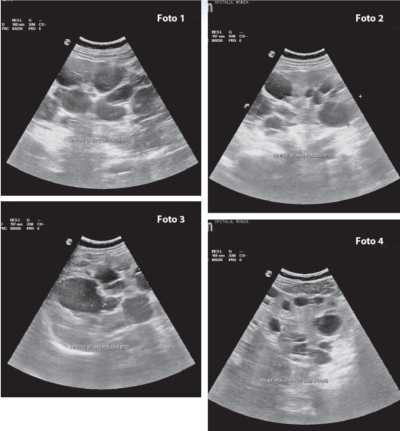

• HTA renoparenchimatoasă – prin ecografie renală, în cadrul căreia se observă forma, dimensiunile rinichilor, grosimea corticalei, obstrucţii de tract urinar, tumori renale;